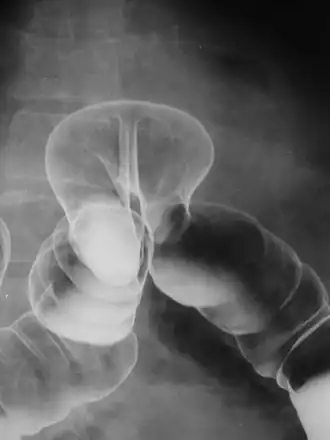

By far the most common hernias (up to 75% of all abdominal hernias) are the so-called inguinal hernias. Inguinal hernias are further divided into the more common indirect inguinal hernia (2/3, depicted here), in which the inguinal canal is entered via a congenital weakness at its entrance (the internal inguinal ring), and the direct inguinal hernia type (1/3), where the hernia contents push through a weak spot in the back wall of the inguinal canal. Inguinal hernias are the most common type of hernia in both men and women. In some selected cases, they may require surgery. There are special cases in which the hernia may contain both direct and indirect hernia simultaneously pantaloon hernia, or, though very rare, may contain simultaneous indirect hernias.[15]

A hiatus hernia is a particular variant of this type, in which the normal passageway through which the esophagus meets the stomach (esophageal hiatus) serves as a functional "defect", allowing part of the stomach to (periodically) "herniate" into the chest. Hiatus hernias may be either "sliding", in which the gastroesophageal junction itself slides through the defect into the chest, or non-sliding (also known as para-esophageal), in which case the junction remains fixed while another portion of the stomach moves up through the defect. Non-sliding or para-esophageal hernias can be dangerous as they may allow the stomach to rotate and obstruct. Repair is usually advised.